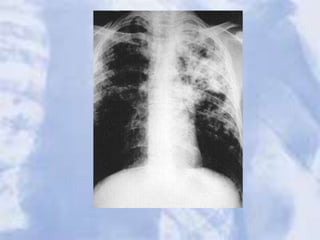

LUL Atelectasis: Loss of heart borders/silhouetting. Notice

over inflation on unaffected lung